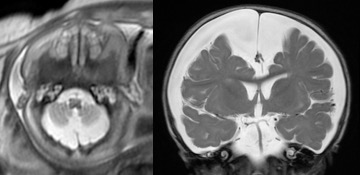

les kystes du plexus choroïde

ils sont de constatation assez banale et généralement non évolutifs. on les trouve tout le long du sillon choroïdien, ils peuvent donc occuper chacun des 4 ventricules ainsi que l’angle ponto-cérébelleux.

le plus souvent, ils ne nécessitent aucune prise en charge.

dans de très rares cas, ils s’associent à un blocage du foramen inter-ventriculaire de Monro, et peuvent nécessiter une intervention (fenestration endoscopique) à la naissance.